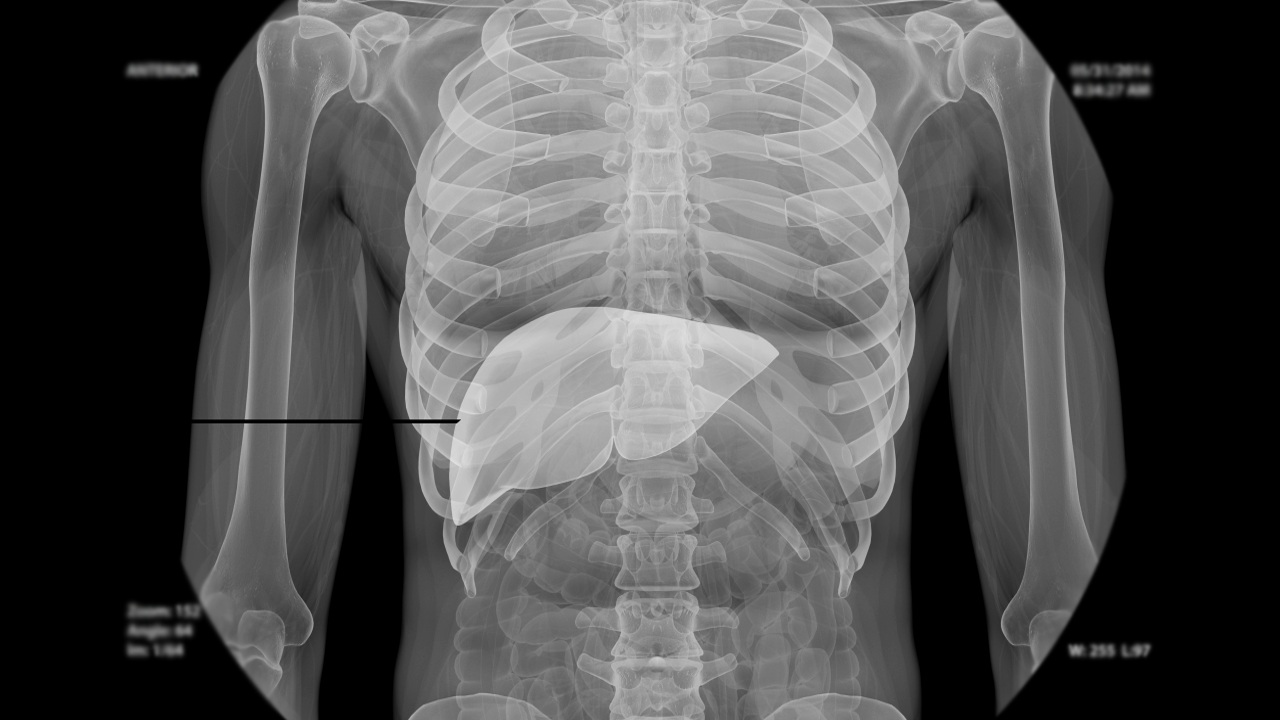

During this outpatient procedure, one or more small samples of tissue are taken from the liver. These tissue samples will be studied under a microscope. A liver biopsy can help identify problems in the liver. If the patient has a liver disease, a biopsy can help doctors determine the type and severity.

The doctor carefully inserts the biopsy needle through the skin and down into the liver. The doctor may guide the needle with the help of an x-ray device called a fluoroscope, which shows moving images from within the body. The doctor uses the biopsy needle to quickly collect a sample. If multiple samples are needed, the doctor may make more than one puncture through the skin.